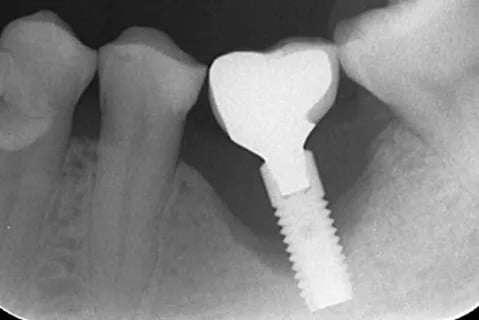

O implante é integrado ao osso através de um processo chamado osseointegração.

Quando essa união está estável, ele funciona como uma raiz artificial fixa.

Se existe movimento, alguma estrutura está falhando — e nem sempre é o implante.

A avaliação clínica e radiográfica define o diagnóstico.